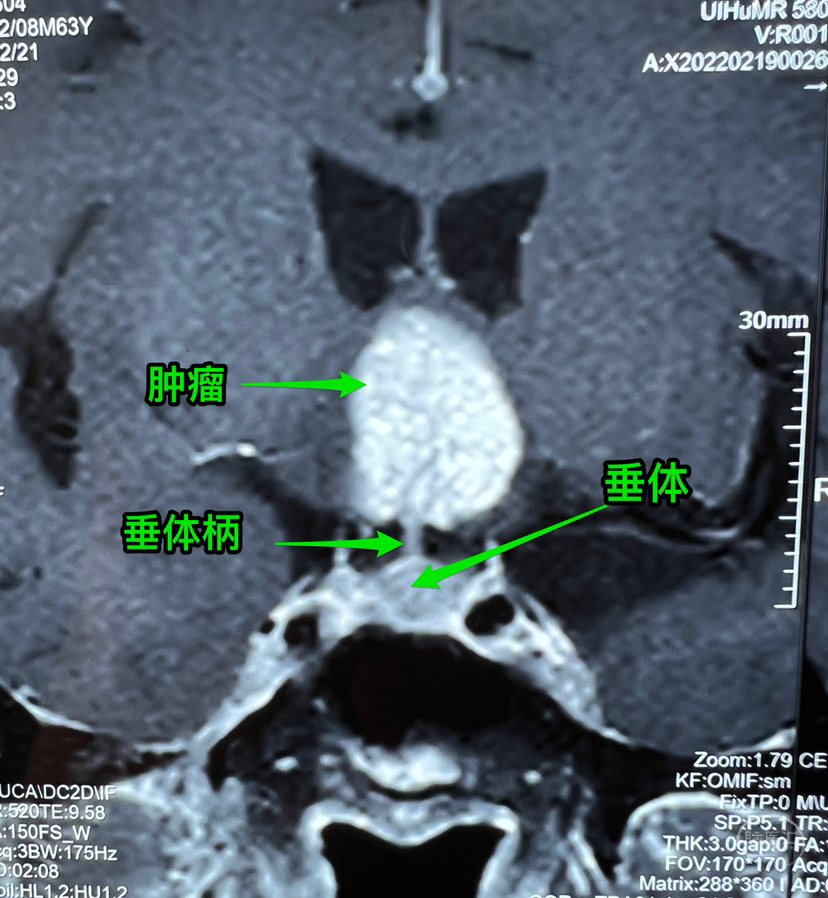

病例简介:中年男性,视力下降,无内分泌及下丘脑损害表现。术前生殖细胞肿瘤相关检查阴性,术中病理:造釉细胞型颅咽管瘤,常规病理尚未报出。

起源点: 术中沿着垂体柄向上切除肿瘤,发现最初肿瘤包绕部分垂体柄,向上探查发现肿瘤起源于垂体柄内,偏一侧,但实际上术中见到肿瘤到了垂体柄内也不一定代表起源就是在这里,如果是生殖细胞肿瘤就有可能是侵入了垂体柄而不是起源于此。“起源点”上方还有一点儿垂体柄,但大多已散开如漏斗结构,问题是:到底是起源于漏斗结节部呢还是下方?不易分辨。

术前